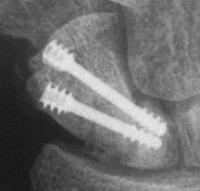

Case 5. Another,same bidirectional technique. Here, I ran the second screw too close to the first, and may have flattened the leading threads - not

ideal. The preop status:

With intercalated iliac bone graft...

Click for larger image

and healing.